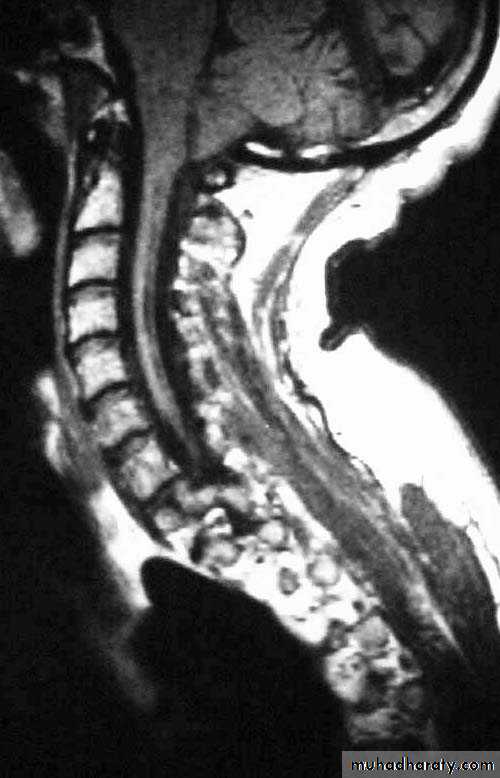

Structural

- Infratentorial

Traumatic

Vascular

Inflammatory

Neoplastic

Degenerative

Infratentorial herniation

• Upward (upward cerebellar or upward transtentorial)

• Tonsillar (downward cerebellar)